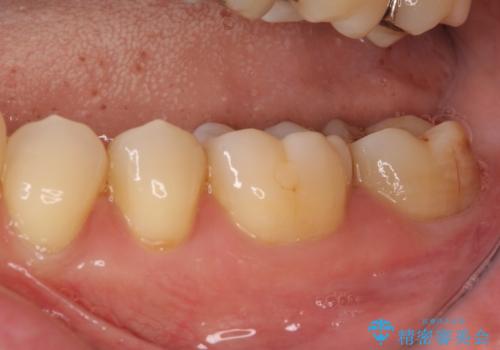

破折部位を除去したところ、外科処置が必要な深さまで破折線が及んでいなかったため、速やかにジルコニアクラウンにて補綴を行うことになりました。

神経が取り除かれた歯、特に奥歯では、歯の破折が起こりやすいので、クラウンによる補綴治療が必要であることを実感した治療でした。